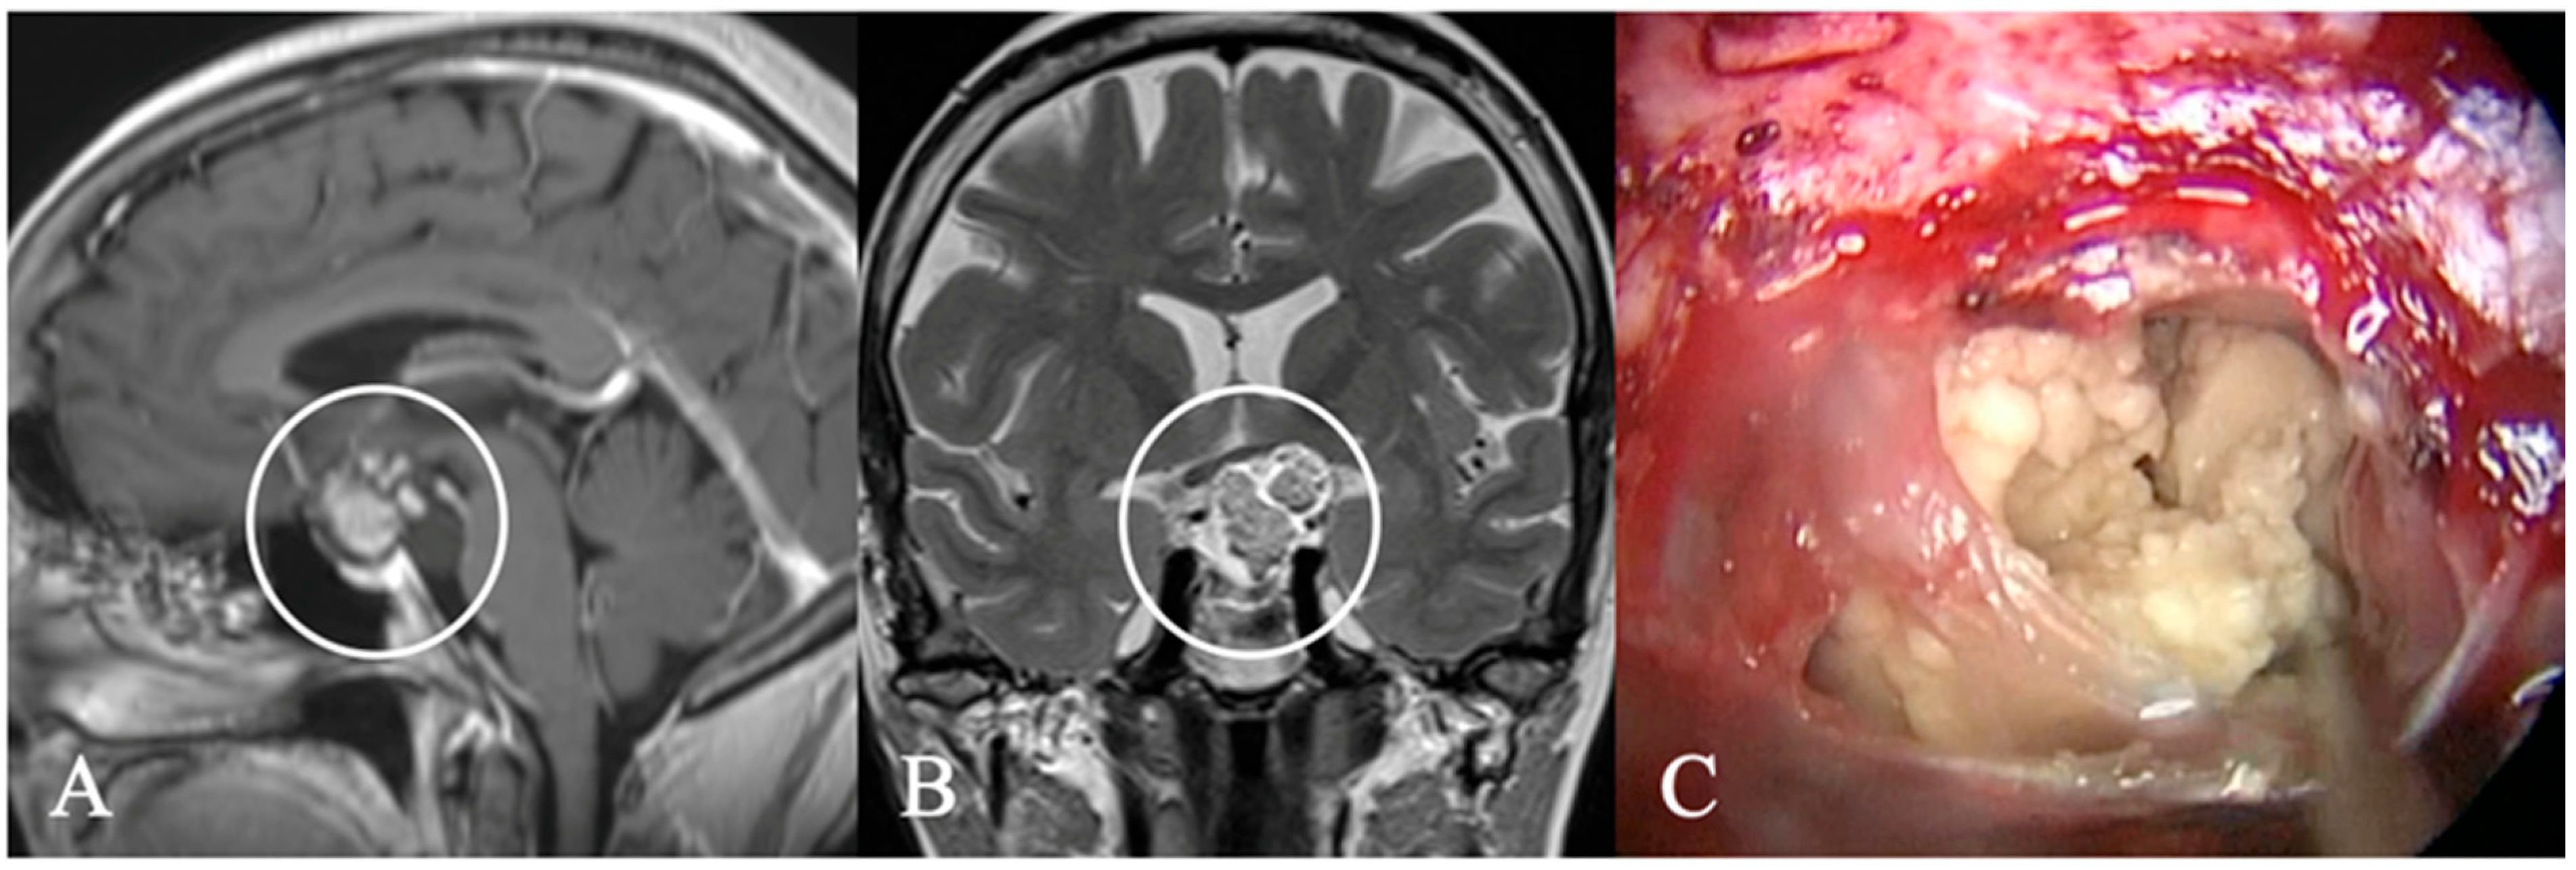

4.2. Differential Diagnoses and Case Presentations